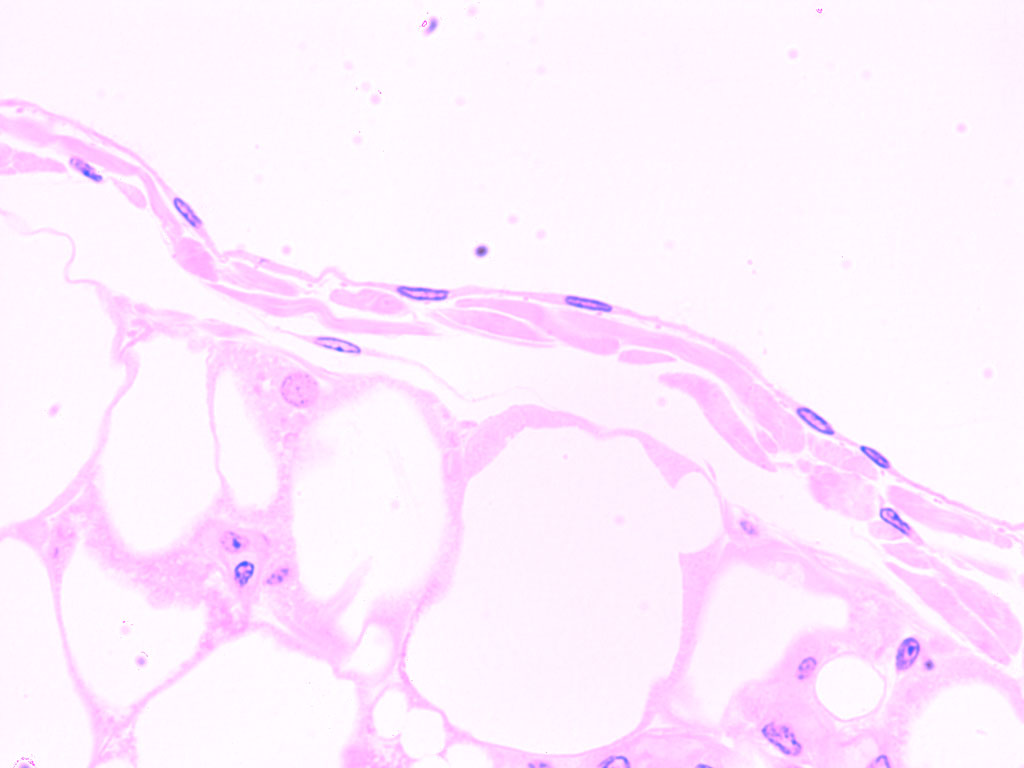

Squamous Epithelial

Thin flat scale-like cells

Simple = one row of cells Stratified = multiple rows

simple squamous epithelium